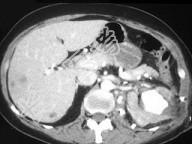

- 单项选择题如图所示,这两个时相提示 ( )

A、肾细胞癌

B、动静脉瘘

C、肾窦对比剂溢出

D、以上都有可能

E、以上都不是